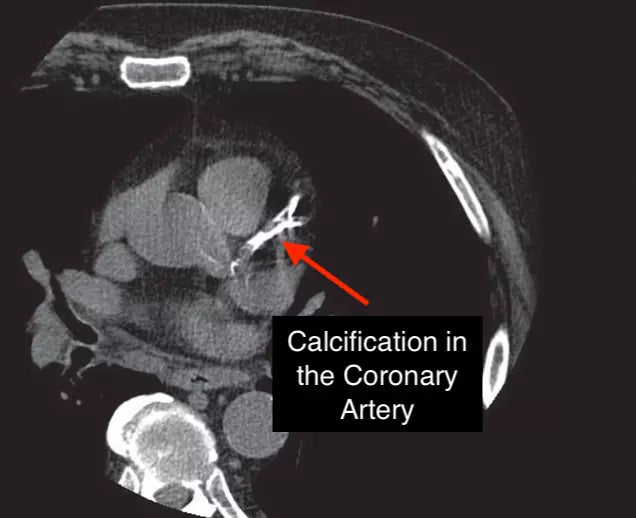

Coronary Artery Calcium Score (CAC)

Prevention is a primary focus at our Tulsa Integrative Medicine clinic. Unfortunately, the first symptom of a heart attack, for most people, is… a heart attack. The Coronary Artery Calcium Score (CAC) is an important test that helps detect cardiovascular disease much earlier than most common cardiovascular tests.

It is essential that we are more aggressive in looking for cardiovascular disease BEFORE there is advanced disease. We have to be much more comprehensive in our testing and screening. Tests such as EndoPAT, Endothelix, CIMT, CV Profiler, and many others are much more sensitive for detecting cardiovascular disease in its very early stages where it is much easier and more cost effective to treat.

In talking about the traditional approach to cardiovascular disease, if a patient does have chest pain, shortness of breath, or any other symptom of cardiovascular disease then a stress test is often ordered, which is very appropriate by the way. However, these stress tests are often not positive until there is at least 60-70% blockage of the coronary artery. The most interesting thing to me is that 68% of heart attacks occur in arteries with less than 50% blockage.2